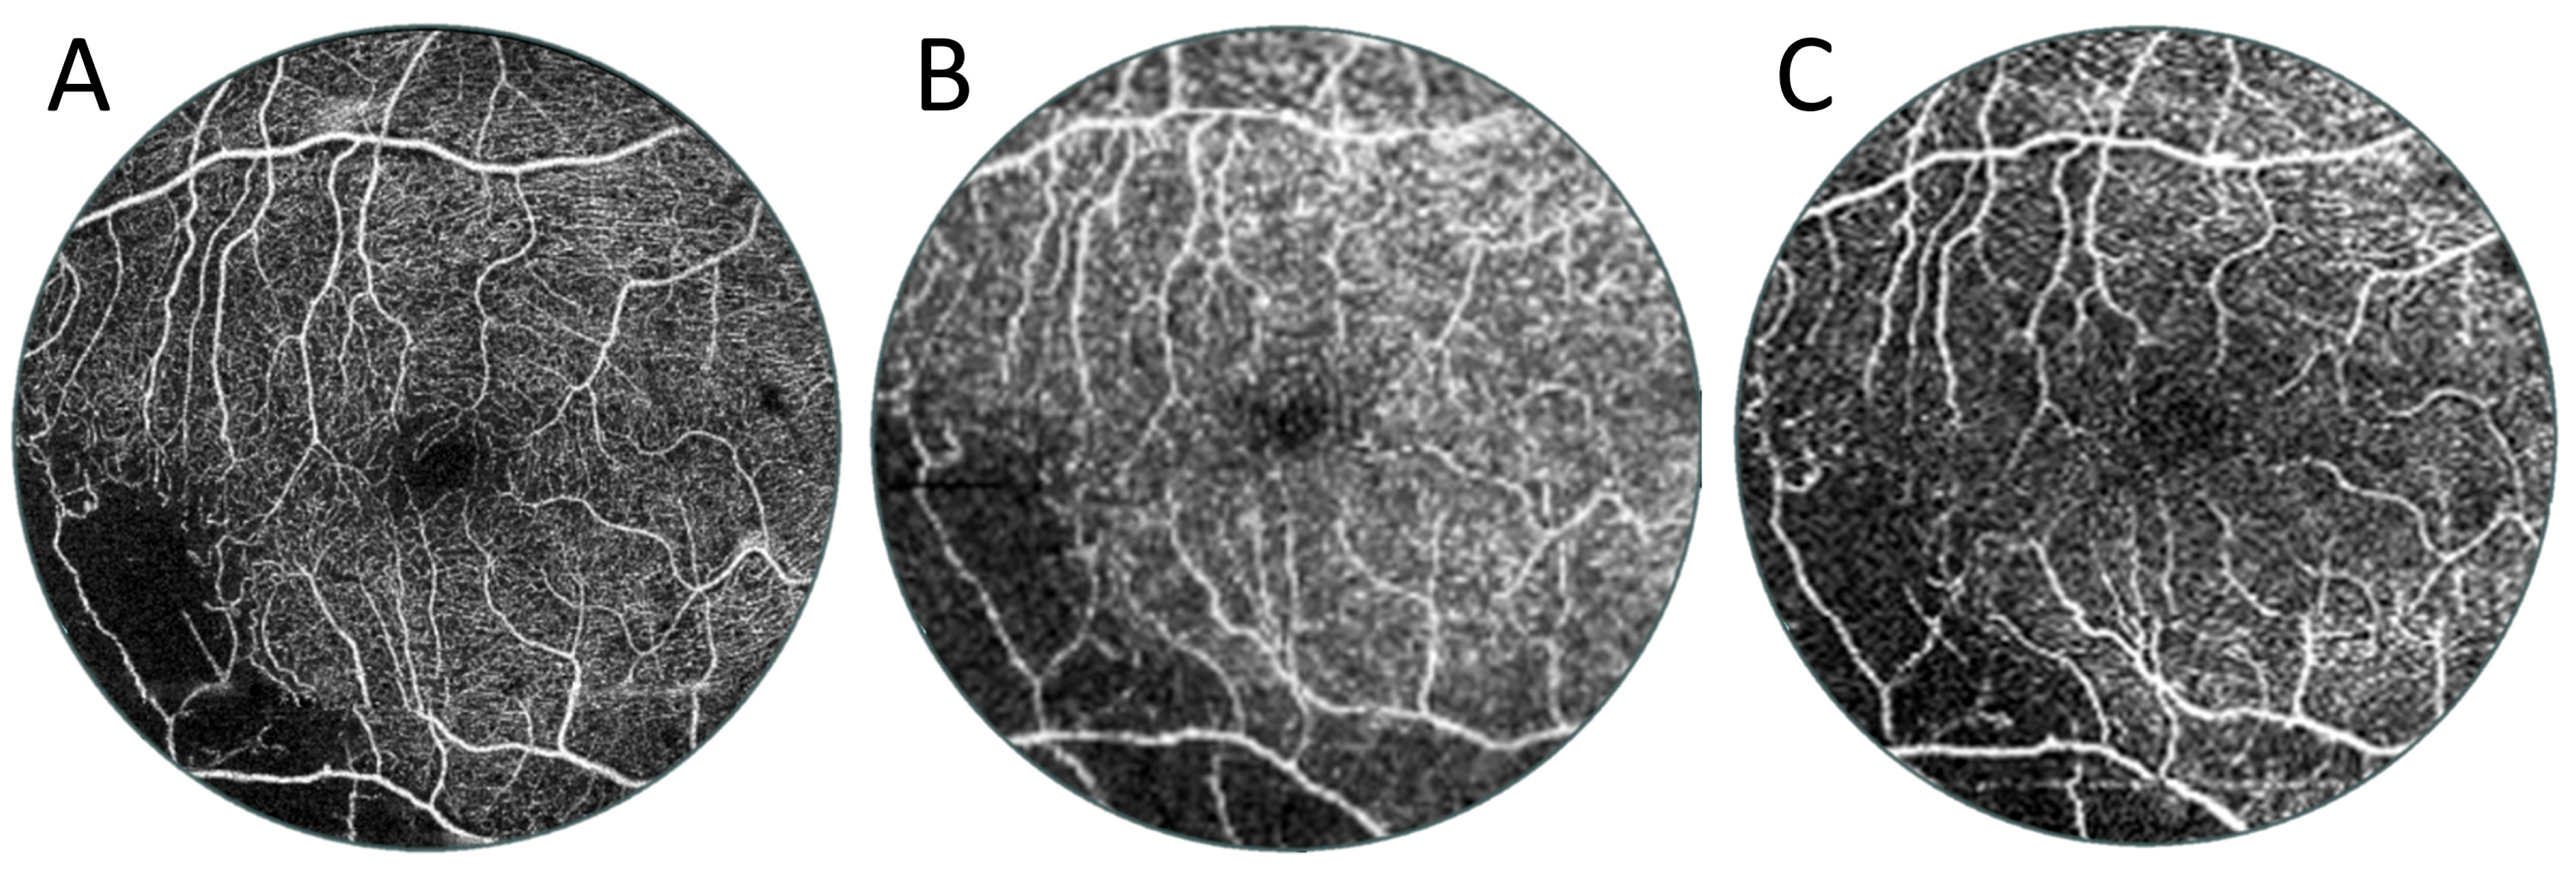

3.2. Angio-OCT Measurements

3.4. UWF Angio-OCT Mosaics